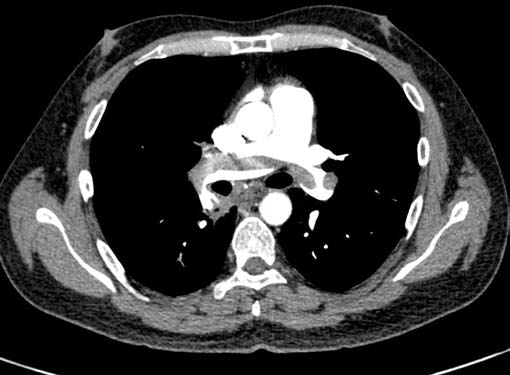

Filling defects (Figs 16A and B) may be seen in main

pulmonary artery (MPA), left pulmonary artery (LPA) and

right pulmonary artery (RPA), interlobar artery, segmental

divisions (Figs 17A and B). On occasions, detection in distal

Right ventricular strain is picked up when RV/LV ratio is

more than one with deviation of interventricular septum to

left.